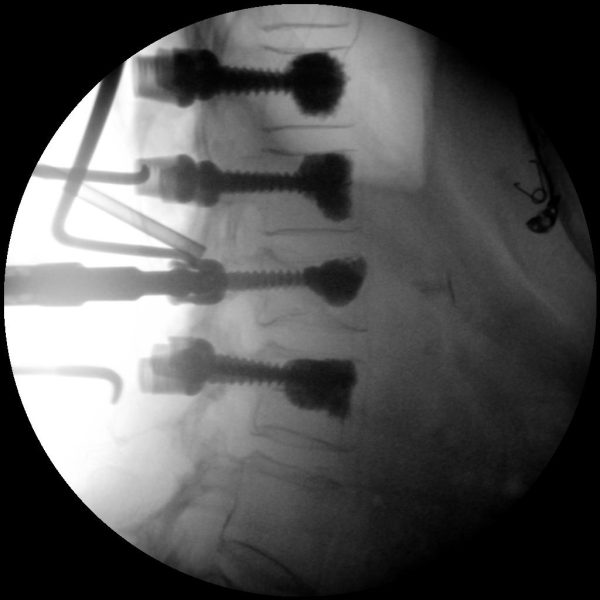

Skan-C uses advanced imaging technology, such as pulsed fluoroscopy and digital subtraction angiography, to provide highly detailed images of the affected area. This allows doctors to perform procedures with increased precision and accuracy, and better patient outcome

Clinical Evidence

Skan-C is a great C-arm for neurology treatments for several reasons